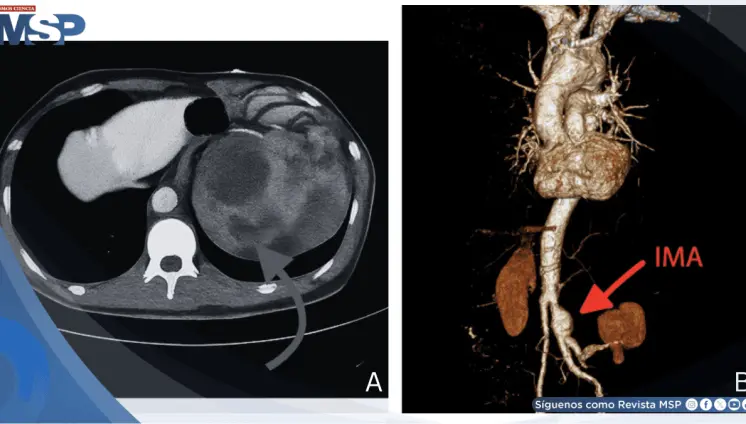

Aneurisma roto simuló infección urinaria: Dolor lumbar e hidronefrosis confundieron el diagnóstico